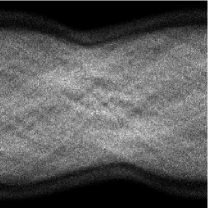

![]() |

\begin{overpic}[height=108.405pt]{figure5a_cbar} \put(0.75,91.0){\small$10$} \put(2.75,3.0){\color[rgb]{1,1,1}{$0$}} \end{overpic} | ![]() |

\begin{overpic}[height=108.405pt]{figure5a_cbar} \put(2.75,91.0){\small$1$} \put(2.75,3.0){\color[rgb]{1,1,1}{$0$}} \end{overpic} | ![]() |

| (a) PET phantom | (b) MRI phantom | (c) PET data |

The phantoms have been used to create artificial data sets for PET and MR imaging. The PET operator is taken from EMrecon [34] and is modeled to match the geometry of one detector ring of the Siemens mMR scanner. It features 56 transversal detector blocks at 8 crystals each, and the gaps between detector blocks have been artificially filled by 56 virtual crystals. For further details we refer the reader to [17]. In order to model the lack of resolution, positron range and scatter in PET, we employ a 2-dimensional Gaussian blur in the image domain with a full width at half maximum (FWHM) of xmm, where we assume that the pixel size in the image is mm. The blurring kernel thus corresponds to a Gaussian with a standard deviation of . The PET data is an instance of a Poisson distribution, where we simulated a total number of million counts. However, we point out that for artificial data the total number of counts is a rather poor criterion to judge a data set, since its quality rather depends on the distribution of those counts across the phantom.

In case of MRI we use undersampled -space data, meaning that we sample the Fourier space only at a few frequencies specified by different geometries. For the sake of simplicity, the MRI operator hence consists of a 2-dimensional Fourier transform followed by a projection onto the geometric pattern of the corresponding sampling (cf. [20] . Note that we do not use a non-uniform Fourier transform since the chosen frequencies are still located on a Cartesian grid. However, the idea and method do not change for non-Cartesian methods. Eventually, Gaussian noise with an energy of approximately five percent of the total energy of the data set is added. We show four different types of undersampling in this work, which can be seen in Figure 6. The samplings introduce different types of artifacts and hence serve different purposes for the joint reconstruction setting which we elaborate on alongside with the results below.

| (a) Full: | (b) Half: | (c) Spokes: | (d) Spiral: |